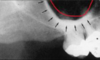

identify the anatomical structure below.

incisive (nasopalatine) foramen